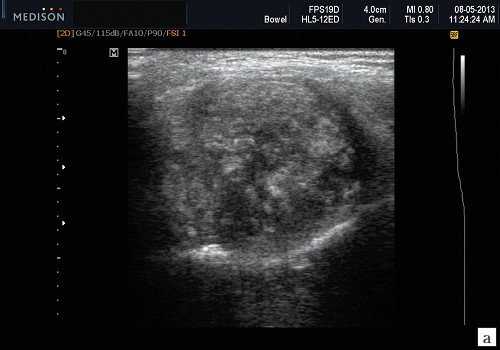

В отечественной и зарубежной литературе встречается много работ, посвященных сиалогии (от греч. Sialon - слюна и logos - учение) - науке о заболеваниях и повреждениях слюнных желез, методах их диагностики и лечения. По данным разных авторов, на долю заболеваний слюнных желез приходится до 24% всей стоматологической патологии. В настоящее время в клинической практике наиболее часто встречаются дистрофические, воспалительные заболевания слюнных желез (сиалоаденозы, сиалоадениты), а также опухоли и врожденные пороки развития слюнных желез. Кроме того, патологические изменения слюнных желез часто сопутствуют другим заболеваниям (сахарный диабет, бронхоэктатическая болезнь, саркоидоз, цирроз печени, гипертриглицеридемия, лимфогранулематоз и др.).

- ультразвуковой метод (является наиболее доступным, безопасным и информативным в процессе дифференциальной диагностики патологического состояния слюнных желез).

Патология слюнных желез

Пороки развития СЖ встречаются редко. Наиболее распространены аномалии размера желез (агенезия и аплазия, врожденная гиперплазия (рис. 2) и гипоплазия), их расположения (гетеротопия, добавочные СЖ), аномалии выводных протоков (атрезия, стеноз, эктазия, кистозная трансформация, дистопии протоков).

Сиаладениты - большая группа полиэтиологических воспалительных заболеваний СЖ (рис. 3). Первичные сиаладениты - сиаладениты, рассматриваемые в качестве самостоятельных заболеваний (например, эпидемический паротит). Вторичные сиаладениты - сиаладениты, являющиеся осложнениями или проявлениями других заболеваний (например, сиаладенит при гриппе). Эхографическая картина при разной этиологии малоспецифична. Этиология имеет клиническое значение в процессе определения тактики лечения.

Рис. 3. Сиаладенит правой поднижнечелюстной слюнной железы.